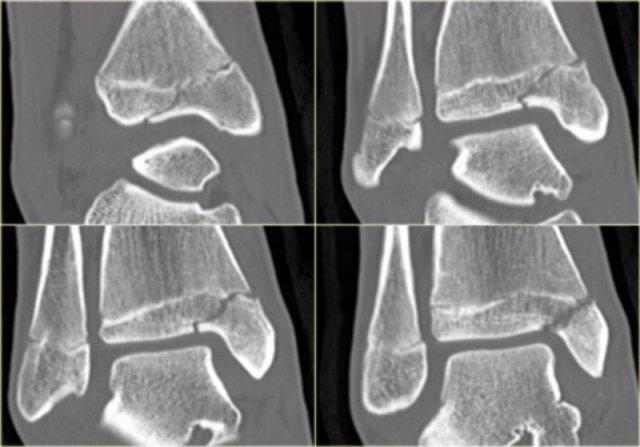

Trong một số trường hợp, gãy mắt cá sau hầu như không nhìn thấy hoặc không thể phát hiện trên phim X-quang và chỉ có thể thấy được trên CT.

Hãy đọc phim X-quang trước, sau đó tiếp tục với hình ảnh CT.

Lưu ý…. có hai đường gãy.

Bạn có thể phóng to hình ảnh bằng cách nhấp vào chúng.

CT cho thấy hình ảnh bong điểm bám tertius tại vị trí bám của dây chằng chày mác sau (mũi tên đỏ).

Sự tương hợp của các mảnh gãy hoàn hảo đến mức không thể nhìn thấy đường gãy trên phim X-quang.

Có thể đường gãy được thấy trên tư thế thẳng (AP) như được chỉ ra bởi các mũi tên đỏ, nhưng điều này còn chưa chắc chắn.

Lưu ý rằng còn có thêm một tổn thương bong điểm bám tại vị trí bám của dây chằng chày mác trước vào xương chày, tức là gãy Tillaux.

Sự kết hợp các dấu hiệu này cho thấy cổ chân không vững.

Cần phải đặt vít cố định khớp chày mác.